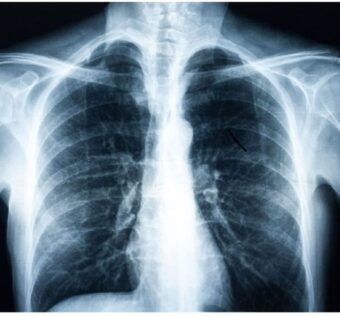

DistilINFO Hospital IT - (Wednesday August 9, 2023) Emory University researchers have unveiled a groundbreaking deep-learning model that utilizes routine chest x-rays and electronic health records to predict early signs of diabetes, even in patients not meeting conventional risk criteria. The AI-driven… |